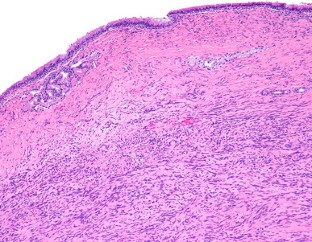

Solitary fibrous tumors (SFTs) are well recognized in the head and neck region, but rarely arise in the sinonasal tract (SNT). Six primary SNT SFTs were identified in the files of Southern California Permanente Medical Group between 2006 and 2017. The patients included five males and one female ranging in age from 33 to 72 years (mean 52 years), most of whom presented clinically with nasal obstruction. Three tumors involved the nasal cavity alone, one involved the paranasal sinuses, and two involved both the nasal cavity and paranasal sinuses. Histologically, the tumors were characterized by a variably cellular proliferation of cytologically bland spindle cells within a collagenous stroma with prominent interspersed branching vessels. Mitotic activity was low (range 0–2 per 10 high power fields) and there was no evidence of pleomorphism or tumor necrosis. Surface ulceration was noted. By immunohistochemistry, the lesional cells were positive for CD34, STAT6 and bcl-2. Clinical follow up information was available for all patients (range 32–102 months; mean 72 months). There were no recurrences or metastases and all were alive with no evidence of disease at last follow-up. SFTs rarely affect the SNT, but should be considered in the differential diagnosis of SNT mesenchymal lesions. Immunohistochemical expression of STAT6 can aid in diagnosis and separation of SFT from other spindle cell lesions occurring at this anatomic site. In combination with cases reported in the literature, primary SNT SFT behave in an indolent manner with conservative treatment.

Fig. 2